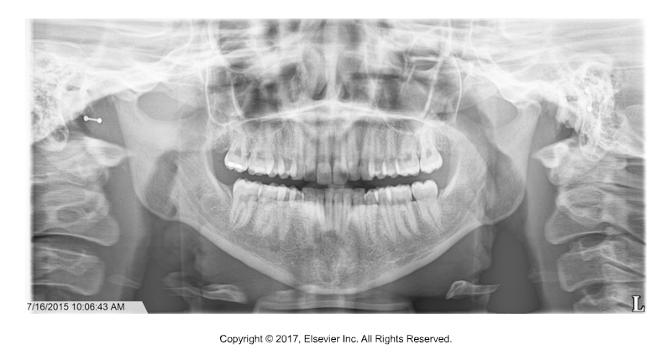

A panoramic radiograph shows a large, blurry, radiopaque shape high on the left side of the image. It appears duplicated and slightly distorted.

Ghost image from jewelry